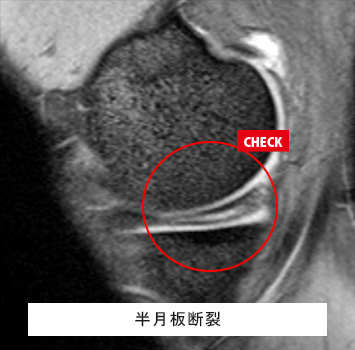

膝(ひざ)MRIチェック

このような方におすすめします。

• 立ち上がりや歩き始めの痛み、階段の昇降時の痛みがある

• スポーツや仕事で膝関節を痛めた、動かしづらい

• レントゲンでは分からない半月板や靱帯の怪我が心配

筋肉と関節痛みのMRIチェック名古屋なら

レントゲン検査では分からない骨、筋肉、腱、関節唇などの様子が

がたった10分の検査で評価出来ます!

長引く膝痛、レントゲンで異常なし

外傷後膝が曲がらない、レントゲンで異常なし

料金(片側):¥17,600(税込)

ご予約はこちら

半月板損傷、前十字靱帯損傷、後十字靱帯損傷、内側側副靱帯損傷、外側側副靱帯損傷、変形性膝関節症、骨軟骨損傷、離断性骨軟骨炎、滑膜炎、ベーカー嚢腫、骨腫瘍、疲労骨折 など